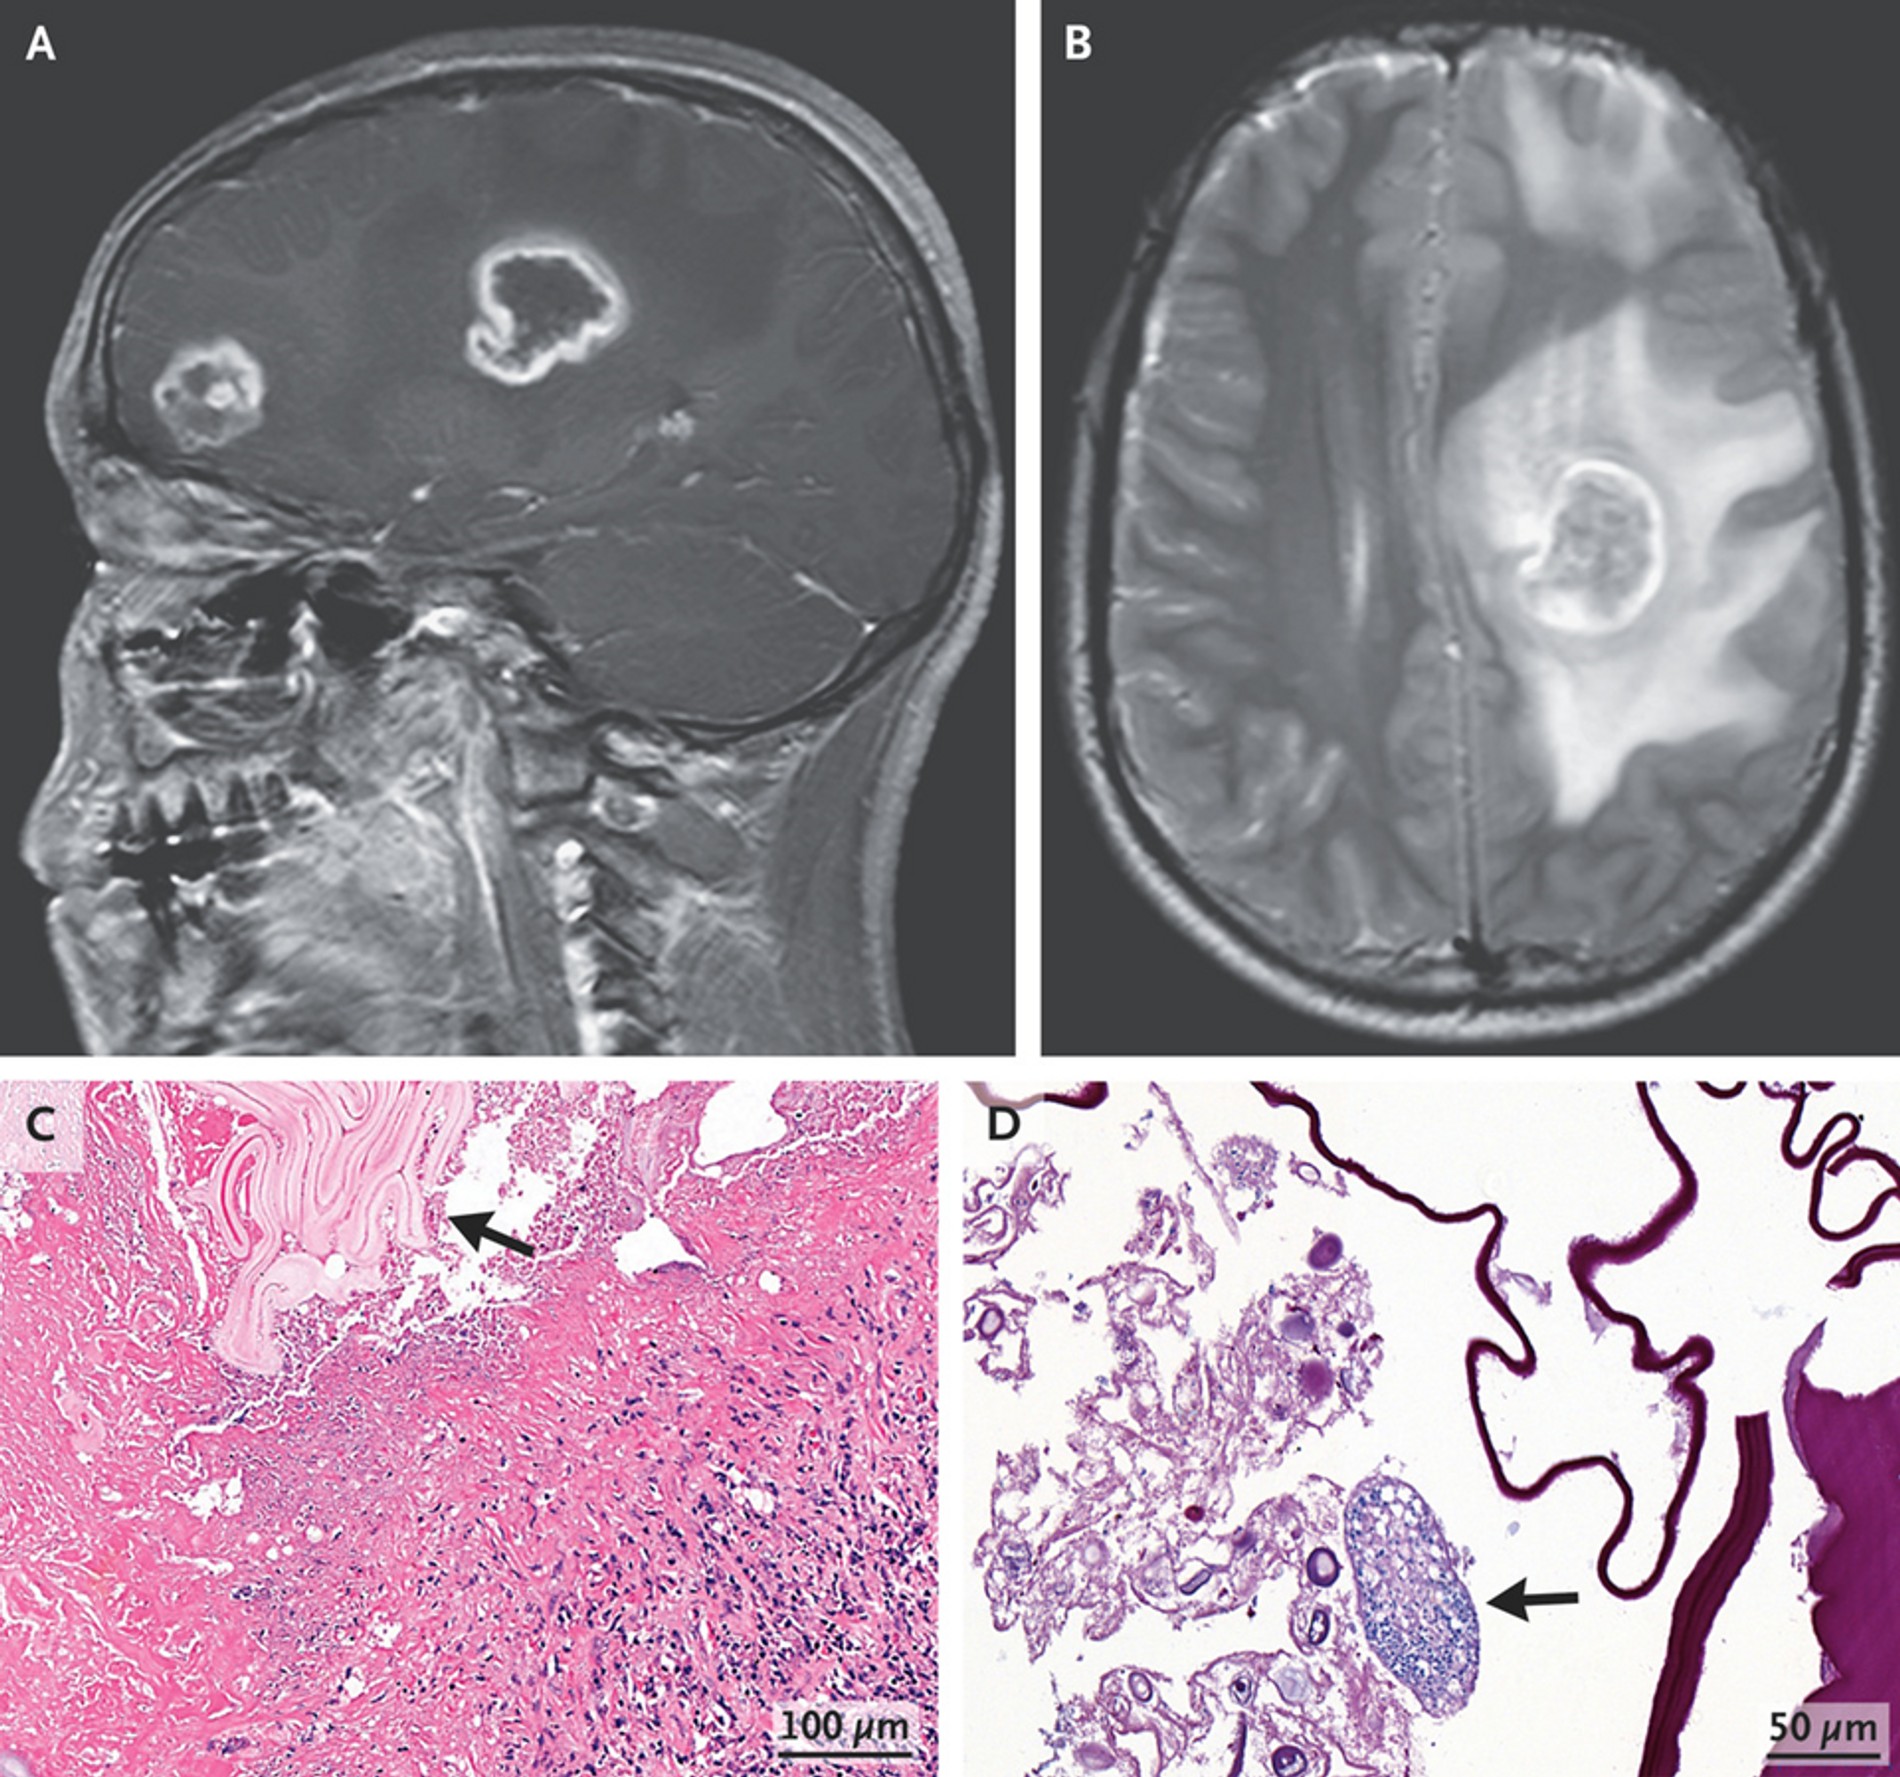

Сразу предупреждаем: эта история не для слабонервных. Китайские врачи описали редкий случай альвеококкоза (паразитарное заболевание), который был обнаружен у 17-летнего подростка. Как сообщает научно-популярное издание N+1 со ссылкой на отчет медиков, пациент поступил в отделение неотложной помощи с жалобами на головокружение, головную боль и мышечную слабость. В ходе хирургического вмешательства в мозге подростка обнаружили материал от ленточного червя — возбудителя альвеококкоза.

Пациенту провели операцию и назначили длительный курс противопаразитарного препарата. Спустя два месяца подросток восстановился и симптомы прошли. Помимо пугающих подробностей, этот случай необычен еще и тем, что в 95% заражений паразит образует кисты в печени или легких, а на центральную нервную систему (мозг) приходится всего 2%. Кроме того, источником гельминтоза являются животные, в основном лисы. Однако пациент заверил врачей, что не контактировал с инфицированными животными.